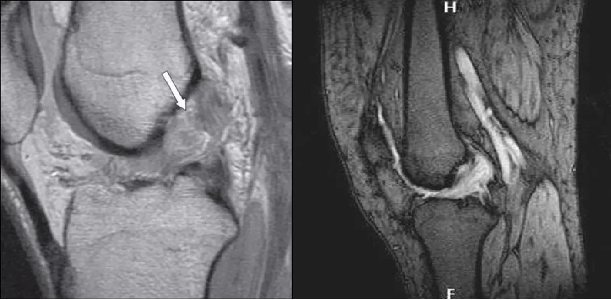

3 级:前交叉韧带完全损伤

在 MR 上表现为韧带信号明显增强,不连续,韧带可能有回缩,韧带走向异常或有假团块等。

前交叉韧带损伤MR分级1级、2级者,多可自愈,所以大多数可保守治疗。而3级损伤的患者,建议手术治疗,但应注意到MR分级的局限性,还应结合膝关节稳定性和个人要求,来决定是否手术。